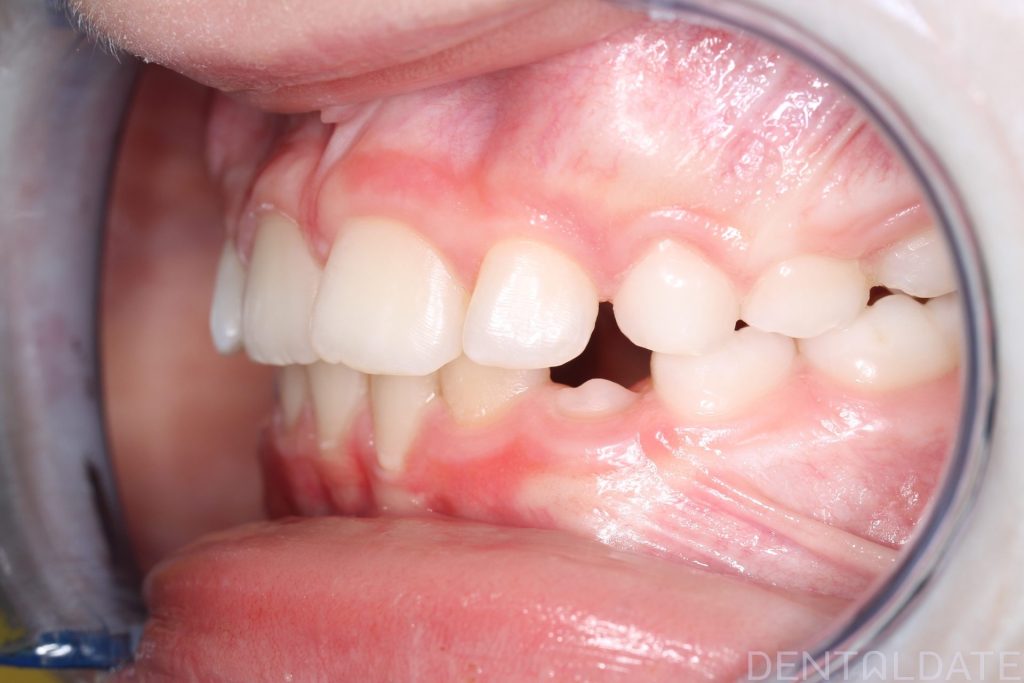

A Haas appliance was placed as the first stage of treatment, followed by the use of a myofunctional appliance.

Because the treatment was initiated right on time, there was no need for 2*4 braces. The child continues to grow and develop normally.